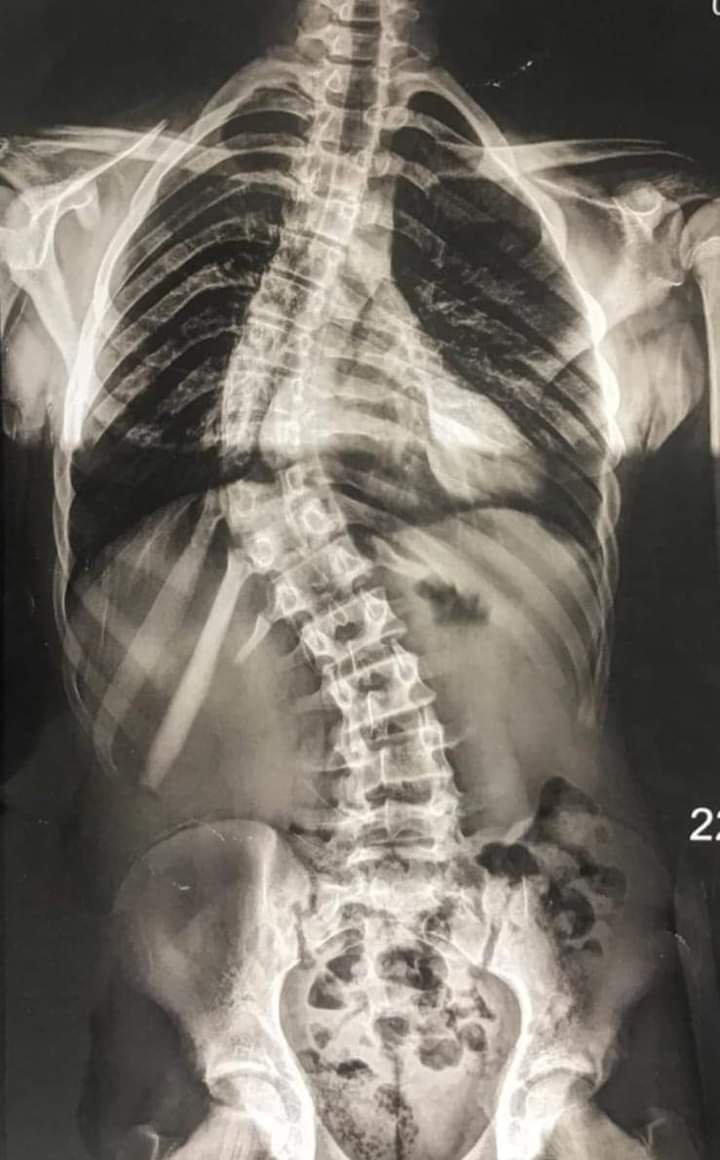

حضر الشاب يعاني من تشوة واعوجاج بالعمود الفقري بدرجه ٦٠ درجه و هذه النسبه تعتبر من النسب العاليه للإعوجاج .

و تم إجراء الجراحه الدقيقة عن طريق تثبيت الفقرات الصدرية و القطنيه بواسطه شرائح و مسامير و عمل قطع عظمى بالمفاصل الخلفيه للفقرات

مع استعدال الاعوجاج كاملا و استخدام احدى التقنيات الحديثه لاعاده تدوير الفقرات المنحرفه عن طريق استخدام احدث المسامير لاعاده تدوير الفقرات

و استغرقت الجراجه حوالى خمس ساعات و تم تركيب عدد ٢٢ مسمار قطنى